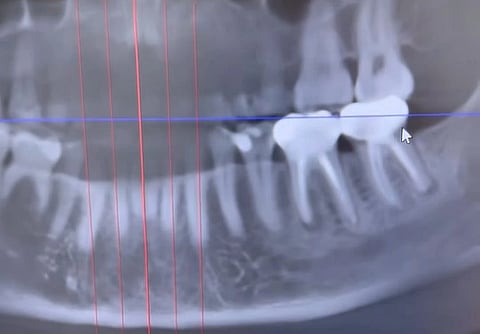

A screengrab of the oral x-ray from the viral video showing the two root canal treated teeth

A screengrab of the oral x-ray from the viral video shows a black and white radiographic image of the lower and upper teeth and a portion of the surrounding jawbone. Two lower molar teeth root canals are seen as opaque as a result of root canal treatment. There are blackish shadows around the roots of these two teeth. @livingwellwithdrmichelle/Instagram

Dr. Michelle Jorgensen, DDS, a dentist in Utah, shared Jacobsen’s x-ray scan online, showing two infected root canals.

According to Newsweek, before Jacobsen’s cancer diagnosis, she had occasionally noticed a subtle, painless, "puffy," almost "squishy" feeling in the gum beneath one of her root canals. After she was diagnosed with invasive ductal carcinoma (IDC), the most common type of breast cancer, and a blood test revealed signs of infection in her bloodstream, her naturopath doctor suggested a dental checkup. Advanced imaging showed both of her root-canal-treated teeth were infected and had abscesses beneath them. After extracting the teeth on October 13, the oral surgeon remarked the infection was even more extensive than imaging indicated.